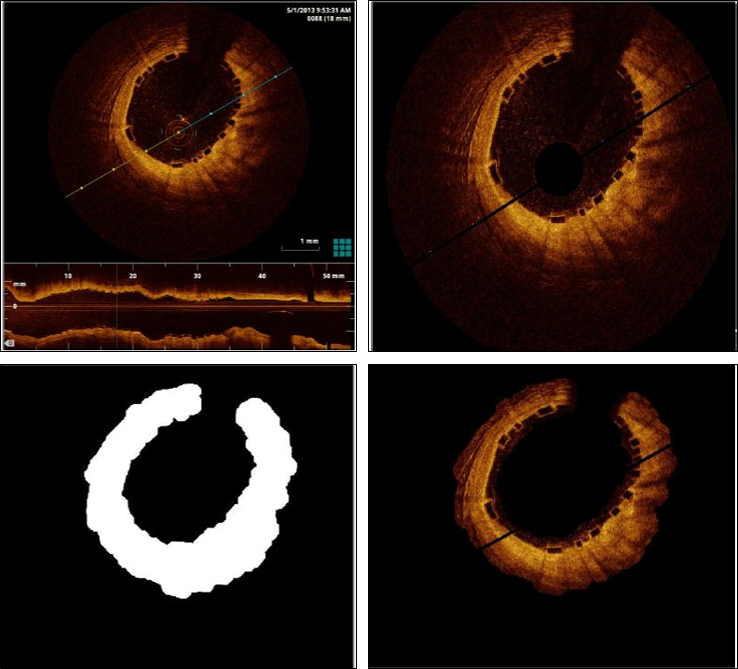

Our region of interest (ROI) is the neighborhood of the vessel wall that appears in high-intensity values. After removing the unnecessary features of the OCT images (as shown in Fig. 2, a typical OCT image contains features that are generally disturbing to the strut detection) to reduce the image to the ROI, we first convert the original RBG OCT image to grayscale image. We find the threshold of the grayscale image by Otsu’s method otsu1975threshold , then convert the OCT to a binary image. Otsu method finds the optimal thresholding by maximizing the inter-class variance between the two classes of pixels into which the image is split. The vessel wall area has higher intensities values, so after thresholding this area becomes white, and we name it AVsubscript𝐴𝑉A_{V}. The rest of the OCT is turned to black. This step is performed by the Matlab function graythresh. To avoid loss of important details, such as the malapposed struts, AVsubscript𝐴𝑉A_{V} is then further expanded to AROIsubscript𝐴𝑅𝑂𝐼A_{ROI} by an appropriate number of pixels: AROIsubscript𝐴𝑅𝑂𝐼A_{ROI} includes AVsubscript𝐴𝑉A_{V} and an additional distance to safely include all the struts. This expansion is performed by the Matlab erosion function imerode which enlarges the white area (Fig. 2). This final white area is used to mask the original image in order to obtain the ROI.

Refer to caption

Figure 2: Top Left: A baseline OCT image. The lower part of the image is the longitudinal review of the stented vessel. Top Right: The OCT image after the unnecessary features are removed automatically. Bottom Left: The binary mask for the extraction of the ROI. Bottom Right: The ROI for strut detection.